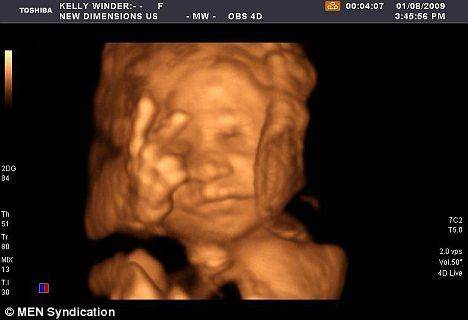

마치 수 개월 뒤에 만날 엄마와 아빠에게 인사를 건네듯, 당당하게 'V'자를 그리며 웃고 있는 27주 된 태아의 사진이 인터넷서 화제다.

영국의 로얄 프레스톤병원에 검진을 받으러 간 임산부인 오웬 스케핑턴 부부는 의사가 건넨 초음파사진을 보고 웃음을 참을 수 없었다.

이제 막 눈·코·입과 손발이 생긴 태아는 매우 편안한 표정으로 몸을 웅크리고 있었다. 놀라운 것은 태아가 고사리 같은 손에서 손가락 두 개를 펼쳐 'V'자를 만든 것.

오웬의 태아 사진은 프레스톤병원에서 큰 관심을 모았다. 병원 측은 오웬 부부의 허락을 구한 뒤 태아의 초음파 사진을 확대해 병원 곳곳에 붙이고, 환자들에게 따뜻한 웃음을 안겨줬다.